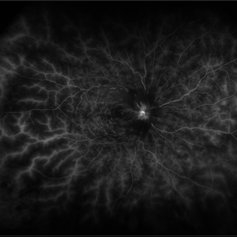

Wyburn Mason Racemose Angiomatosis

Color fundus montage of an 13-year-old female with arteriovenous malformation (Wyburn Mason Racemose Angiomatosis) affecting her right eye. The retinal arteriovenous malformation appears to be stable. She presented with NLP in the eye, strabismus, and peripheral retinal ischemia. She is at risk for neovascular complications; however, she is currently being treated with Sirolimus. Since she is on this systemically, there is no need to perform intraocular anti-VEGF injections or PRP laser. She also presented with optic atrophy affecting her left eye, secondary to chiasmal involvement of arteriovenous malformation. She has had a potential progressive visual field loss involving the temporal aspect of her visual field from the left eye. There is sector optic atrophy. Presumably, this is due to a compressive effect of her arteriovenous malformation on the nasal nerve fiber layer (corresponding to the temporal visual field) crossing to the right occipital cortex at the chiasm.

Photographer: Olivia Rainey

Imaging device: Topcon 50dx

Condition/keywords: arteriovenous malformation, color fundus photograph, color photo, montage, peripheral ischemia, Sirolimus